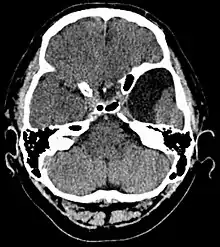

Arachnoid cyst as seen on a CT image of the brain

Axial CT showing a typical arachnoid cyst left temporal

Diagnosis is principally by MRI. Frequently, arachnoid cysts are incidental findings on MRI scans performed for other clinical reasons. In practice, diagnosis of symptomatic arachnoid cysts requires symptoms to be present, and many with the disorder never develop symptoms.